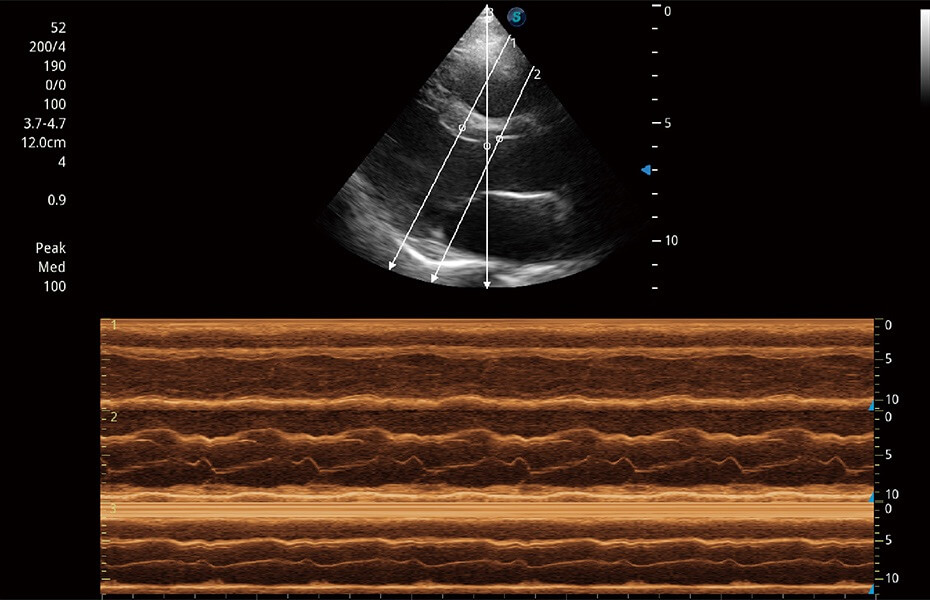

ProPet 60 作为一款高端台式动物超声设备,为动物医生的日常诊断提供了一系列贴合动物临床需求、解决临床实际问题的高级成像功能。凭借全系列高清探头,满足医生对腹部、心脏、生殖、浅表、肌骨等成像的所有需求,切实帮助您提升检查效率,提高诊断信心。

兽用彩色多普勒超声诊断系统